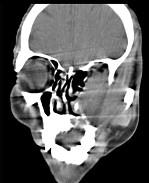

问题 男,65岁,左眼球突出近1年,鼻涕带血,面颊部隆起,同时面颊部有麻木感,CT检查如图,最可能诊断为()

选项 A.上颌窦息肉 B.上颌窦血管瘤 C.上颌窦囊肿 D.上颌窦癌 E.骨肉瘤

答案 D